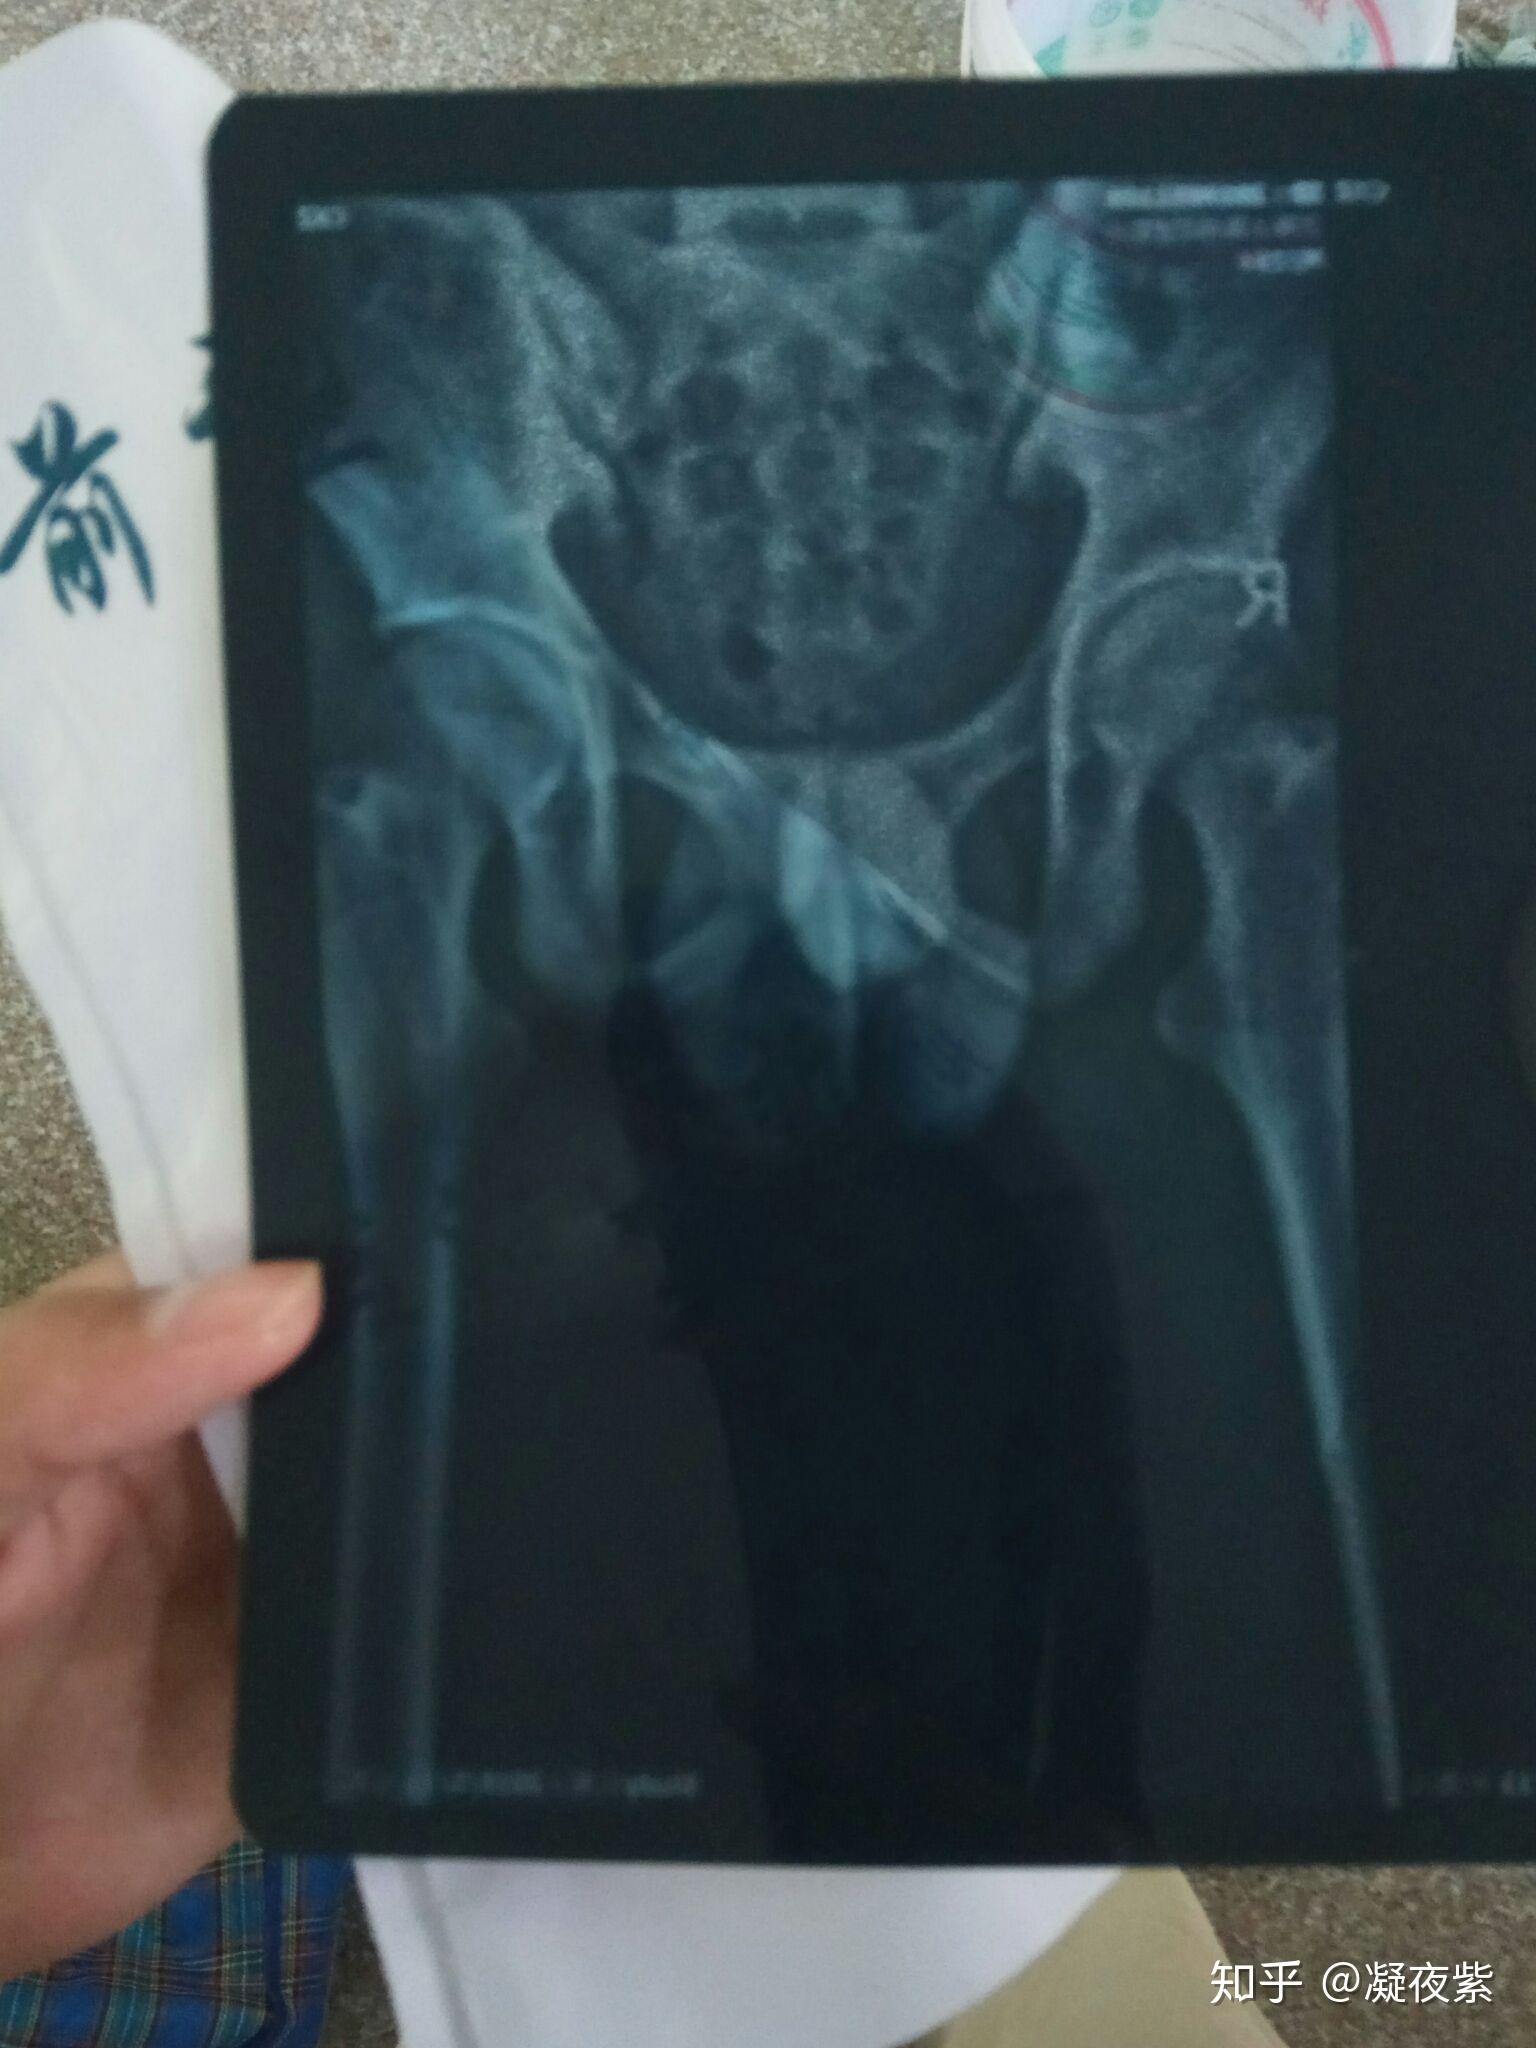

看图论病(尾椎骨折)

图片尺寸1728x2304